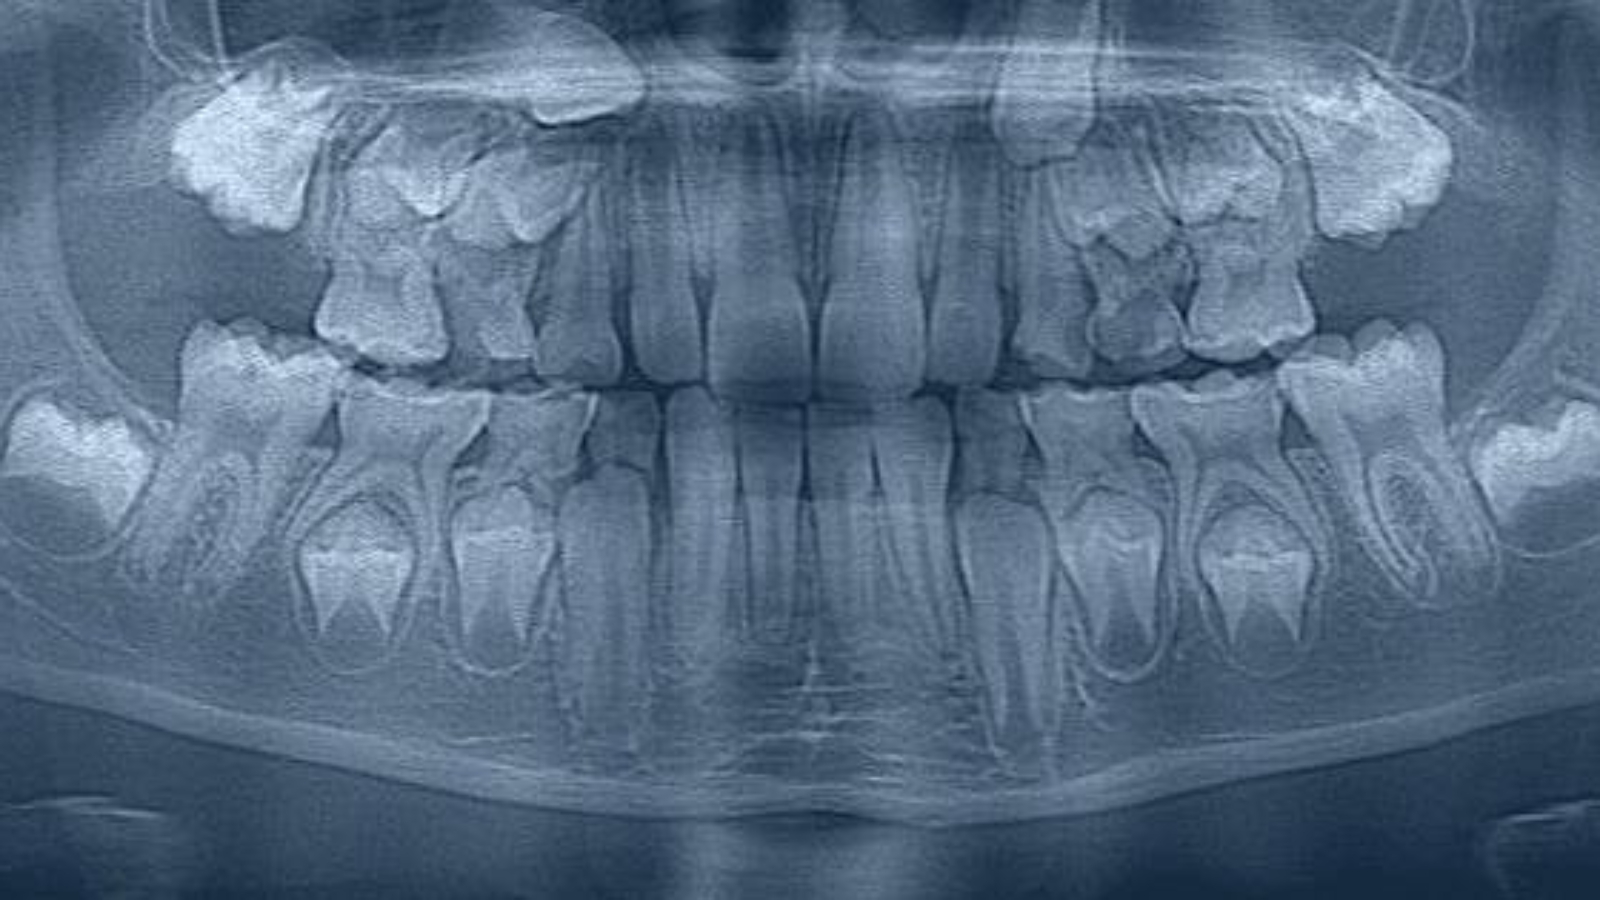

Diagnosis of supernumerary teeth requires a comprehensive approach, because their presence is not always obvious during routine examination. In a number of cases, they may be located within bone tissue and remain clinically silent in the early stages. At DentalClinic24, diagnosis is based on both clinical signs and additional imaging methods that make it possible to determine the exact position and characteristics of the tooth.

Particular importance is attached to evaluating the way in which a supernumerary tooth affects surrounding structures. It is essential to determine whether it creates obstacles to eruption, exerts pressure on adjacent teeth, or alters the anatomy of the bone tissue. At DentalClinic24, analysis is performed not only on the basis of the presence of the additional tooth itself, but also according to its clinical impact.